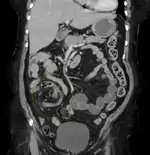

Volvulus with gangrene of the sigmoid

Sigmoid